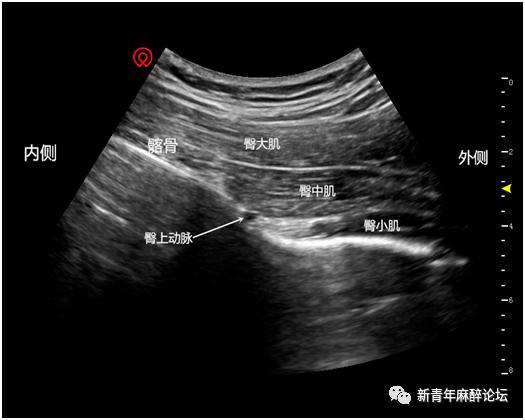

髂筋膜阻滞超声图

髂筋膜阻滞超声图,髂筋膜间隙阻滞

髂筋膜间隙阻滞

髂筋膜的解剖结构

髂筋膜间隙解剖

髂筋膜阻滞解剖图

髂筋膜解剖

高位髂筋膜阻滞超声图

高位髂筋膜阻滞领结征

股神经阻滞超声图

超声引导下髂筋膜阻滞

髂筋膜阻滞